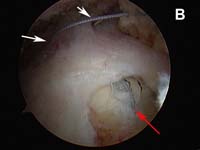

As tears become larger, they deform and the tendon tissue "shrinks". Thus, larger tears need to be refashioned, repaired side-to-side, or "zipped" closed using a technique called margin convergence. This technique is analogous to zippering shut an open tent flap. The rotator cuff tissue is freed from a scarred, retracted position and repaired side-to-side to ‘close the tent flap’ and restore the tissue over the top of the humeral head. (See Fig.4 and Fig.10) The repaired cuff tissue is then fixed to the site it originally tore away from using specially-designed implants called suture anchors. These are metallic or absorbable plastic devices that secure sutures to the bony attachment. The sutures are then sewn through the torn edge of the cuff to complete the repair.

- The edge of the cuff tear must be brought back to its normal position without undue tension. This process is accomplished using techniques called mobilization or in larger tears, a technique called margin convergence. (See Fig. 4).